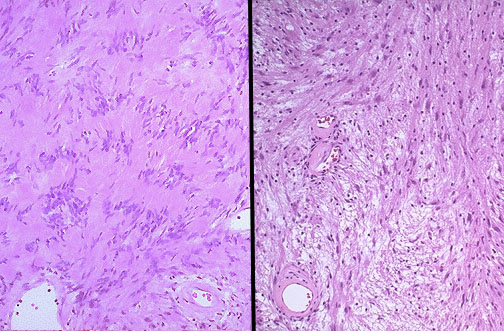

| These are the classic microscopic appearances of a schwannoma, which is benign. Note the more cellular "Antoni A" pattern on the left with palisading nuclei surrounding pink areas (Verocay bodies). On the right is the "Antoni B" pattern with a looser stroma, fewer cells, and myxoid change. |